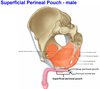

3: Crus

4: Bulb of the vestibule